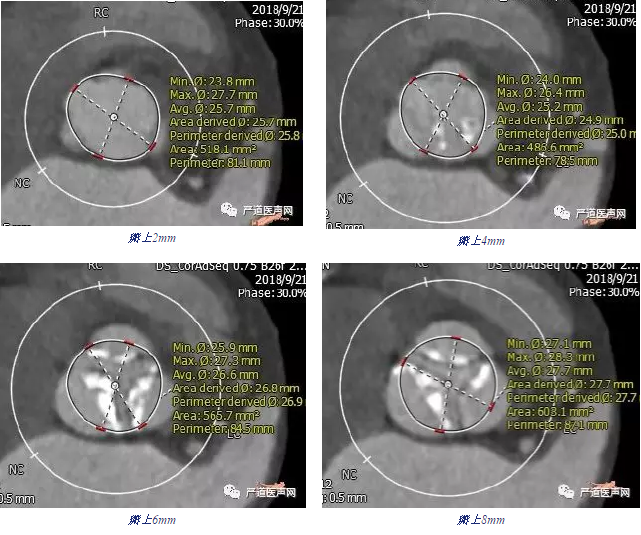

◆ 分别选取瓣上2mm, 4mm, 6mm, 8mm四个平面进行测量:

◆ 根据瓣环尺寸及瓣上多平面测量结果予以25mm球囊扩张后经左颈动脉植入29mm的Venus-A瓣膜,结果满意。